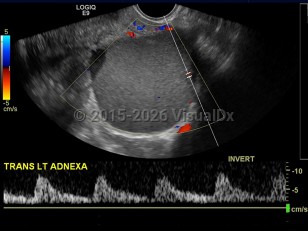

EndometriosisEndometriosis

Ovarian cancerOvarian cancer

Salpingitis

Pelvic inflammatory disease

Renal nutcracker syndrome